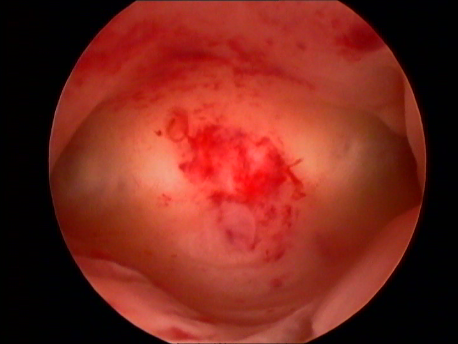

- Abnormal uterine bleeding: Heavy, prolonged or irregular bleeding can be caused by submucous fibroids and polyps.